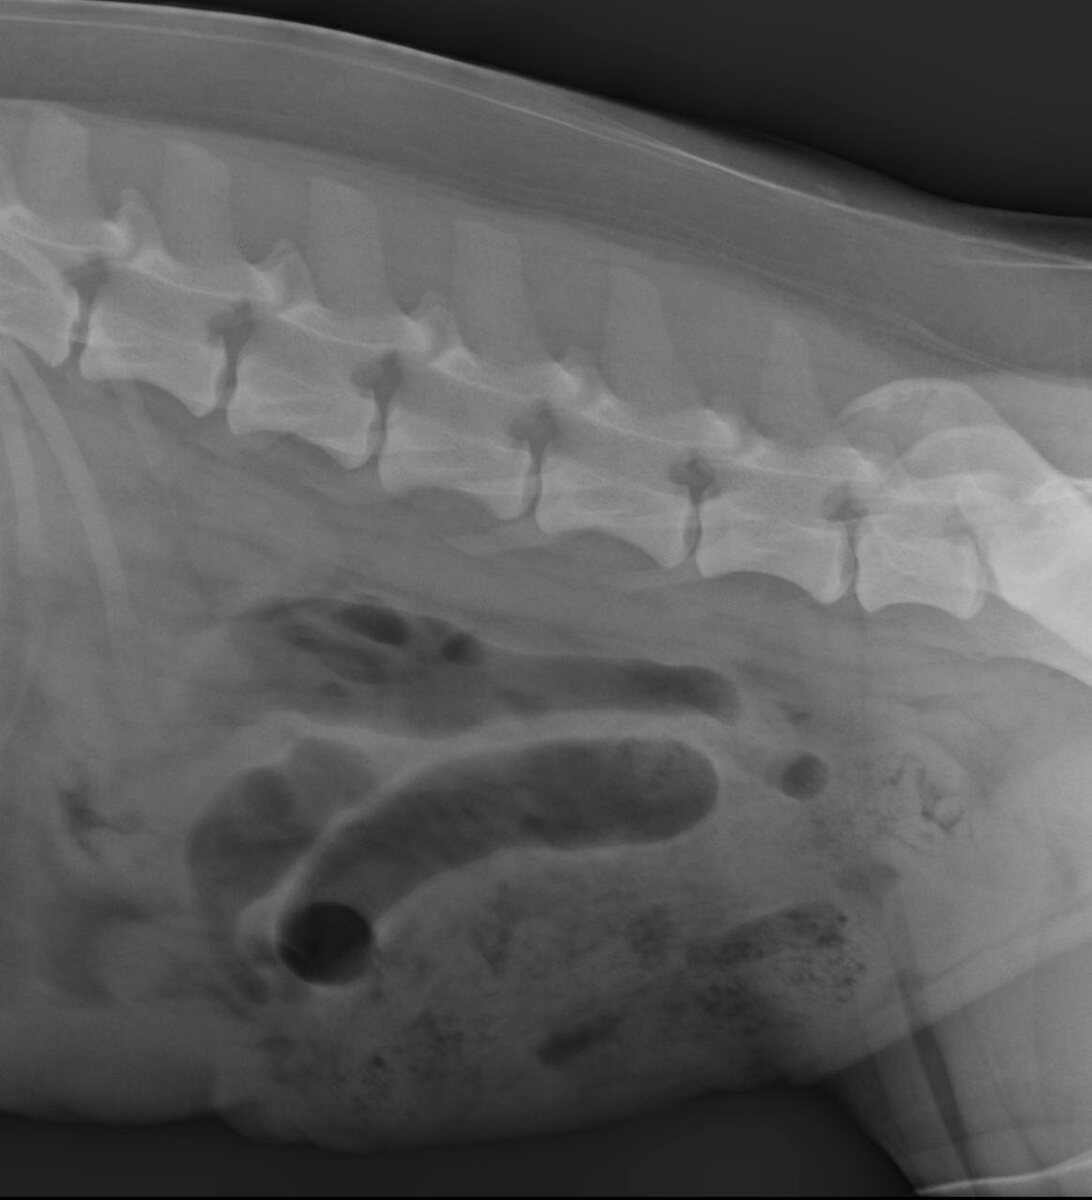

Реджик на прогулке грыз ветки и кору. Появилась рвота водой и ветками. Так он стал пациентом врача Брусницыной Ксении Анатольевны в клинике «Ветдоктор» в г.Верхняя Пышма. При клиническом осмотре доктор отметил дискомфорт при пальпации живота. По результатам УЗИ брюшной полости и рентгенологического исследования выявлено подозрение на непроходимость кишечника. На приеме Реджик был активен, со слов владельца стул был оформленный. Поэтому питомцу назначили необходимое лечение и отпустили домой. Сейчас у Реджика все хорошо! Желаем ему здоровья! 🧡 #ветдоктор

По результатам УЗИ брюшной полости и рентгенологического исследования выявлено подозрение на непроходимость кишечника.